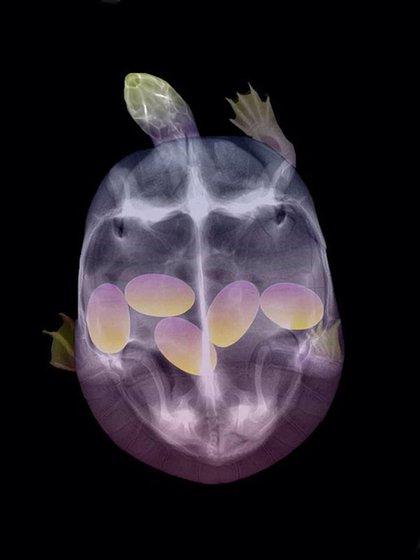

哈~這其實是動物懷孕的照片啦!美國《boredpanda》網站最近整理了一系列懷孕動物的X光照,從最常被人類飼養的貓、狗,乃至於蝙蝠、浣熊等都有,雖然小動物的誕生應該是可愛而溫馨,不過單看這些滿肚骨骸的X光照,還是覺得有點驚悚和詭異啊!

烏龜